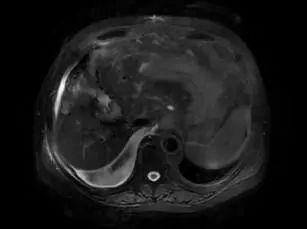

肝脏穿刺活检病理证实为肝细胞癌。

图3. 穿刺病理HE染色特征